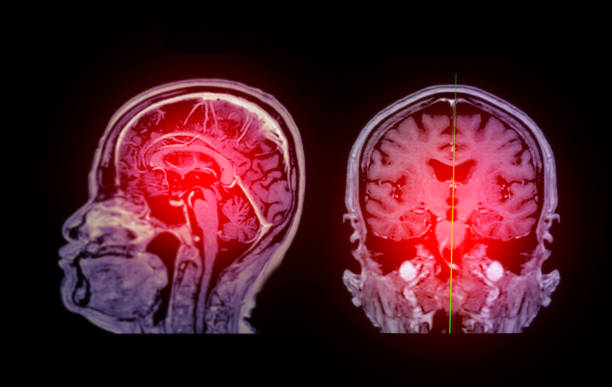

截止3月26日,國家藥品監督管理局藥品審評中心,共計許可5款間充質干細胞新藥用于治療缺血性腦卒中的臨床研究。這標志著我國在缺血性腦卒中的治療領域邁出了重要一步,將為眾多患者帶來了新的希望。

缺血性腦卒中,又稱腦梗死,是一種因腦部血液循環障礙導致的腦組織壞死疾病。它給患者帶來的不僅是身體上的痛苦,更是心理上的巨大壓力。